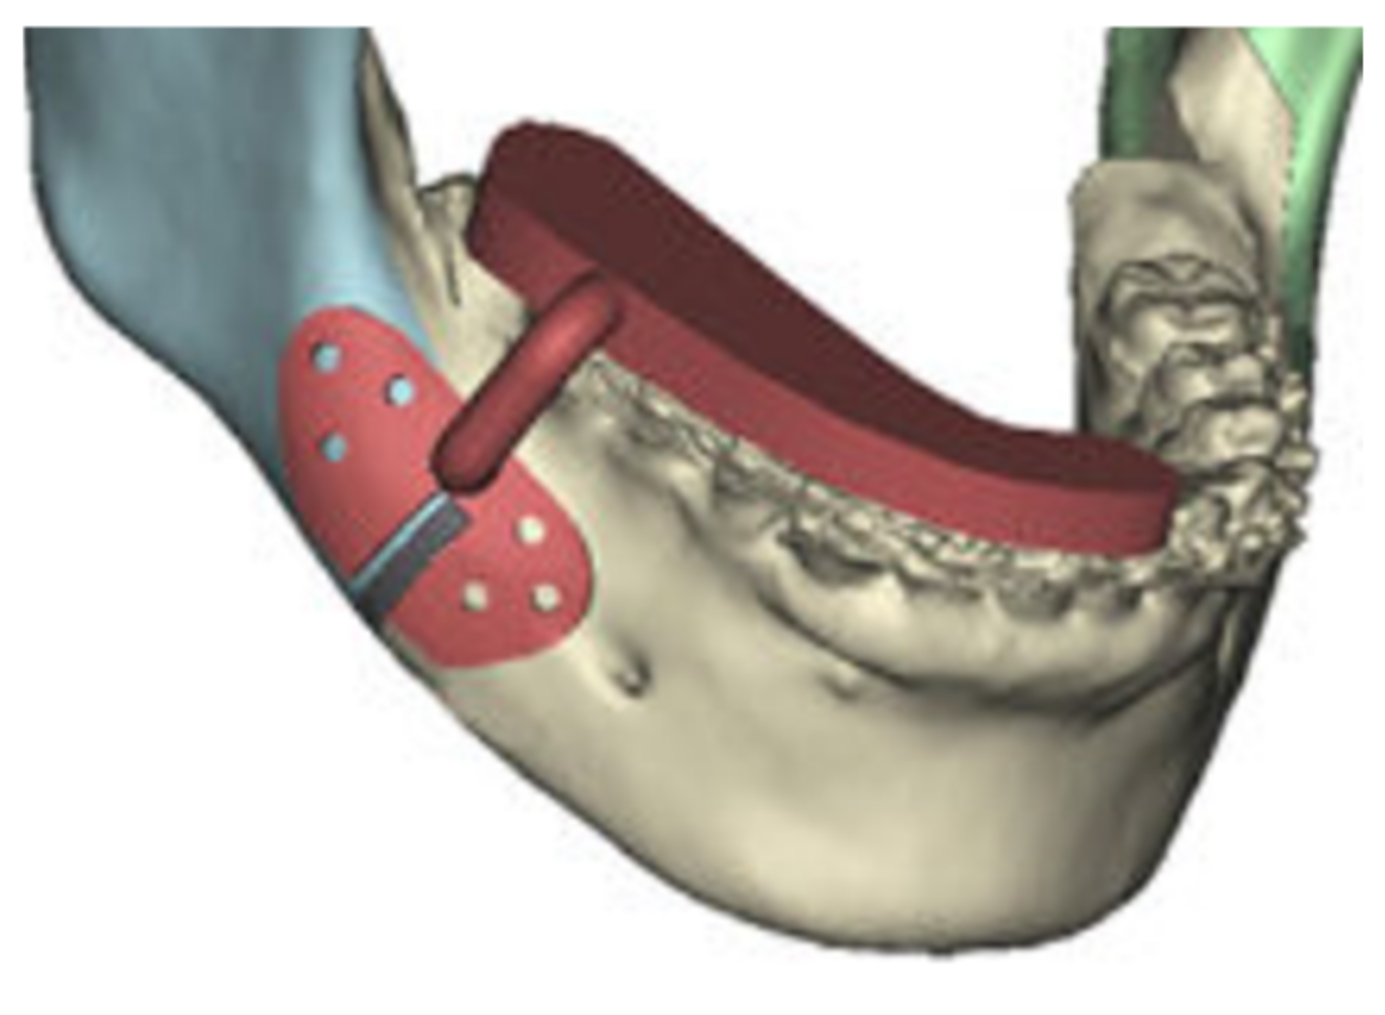

In the following figures, the medical images, orthopanoramic images (Figure 6 and Figure 7) before and after an orthognathic surgery, the implanting screws (Figure 8), and a digital reconstruction (Figure 9) are shown.

Figure 8. Implanting screws.